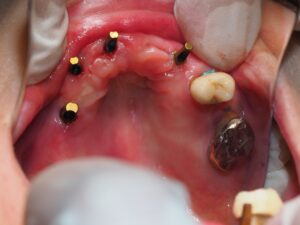

上顎インプラント前歯3本、臼歯に1本埋入

(京セラ、レリオス、ボーンレベル32の10を三本、37の6を一本埋入)

初期固定全て良し、音良し。

CT、パントモすべて良好。

アバットメント